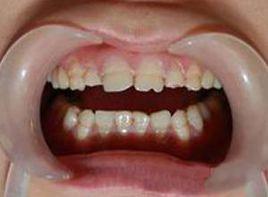

本病徵累及乳齒與恆齒,這些表現在出生後長牙時即可出現。牙齒較小,呈半透明狀,色澤棕黃或橙黃。質地脆弱,容易折斷,但無鬆動現象。全部或大部分牙齒可逐漸被磨短。

1.輕症釉質形態正常,無實質性缺損,釉質呈白堊色不透明,表面疏鬆粗糙,有時呈黃褐色。

2.重症釉質實質性缺損牙齒表面有帶狀或窩狀的凹陷,變色呈白堊色或黃褐色,嚴重者無釉質形成或牙冠形態改變或縮小。